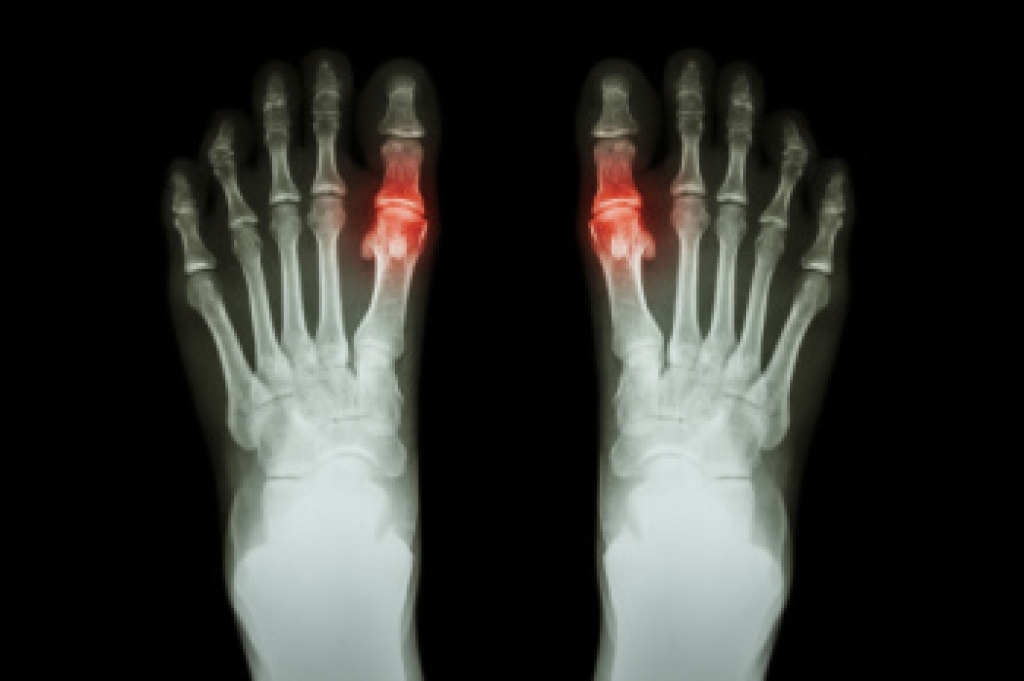

Diabetic foot ulcers, or DFUs, are open sores that often develop in the ball of the foot, heel, or tips of the toes. Diabetic foot ulcers result from nerve damage and poor circulation caused by prolonged high blood sugar levels, which impair sensation and slow healing. Without proper care, DFUs can lead to serious infections, gangrene, or limb loss. The Wagner classification system is commonly used to assess the severity of DFUs. It includes six grades: Grade 0 indicates no open lesions but a high-risk foot. Grade 1 refers to superficial ulcers. Grade 2 involves deeper ulcers that extend to ligaments or muscles. Grade 3 signifies ulcers with bone involvement or abscess. Grade 4 describes localized gangrene of the forefoot. Grade 5 represents extensive gangrene of the entire foot. These stages help a podiatrist determine the best course of treatment, including wound care and infection management, to prevent further complications. If you have developed a foot ulcer related to diabetes, it is suggested that you make an appointment with a podiatrist for regular exams and necessary treatment.

Diabetes affects millions of people every year. The condition can damage blood vessels in many parts of the body, especially the feet. Because of this, taking care of your feet is essential if you have diabetes, and having a podiatrist help monitor your foot health is highly recommended.